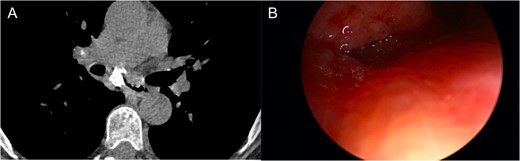

One-year after her original presentation, the patient presented to the emergency room with worsening cough and choking with oral intake. A CT scan of chest revealed a fistula between the right mainstem bronchus and esophagus (Fig. 2A). The patient underwent rigid bronchoscopy revealing a 2-cm defect on the medial wall of the right mainstem bronchus, ~1-cm from the main carina (Fig. 2B). A CT esophagram confirmed extravasation of oral contrast into the tracheobronchial tree (Fig. 3).

Esophagram revealing extravasation into the tracheobronchial tree.